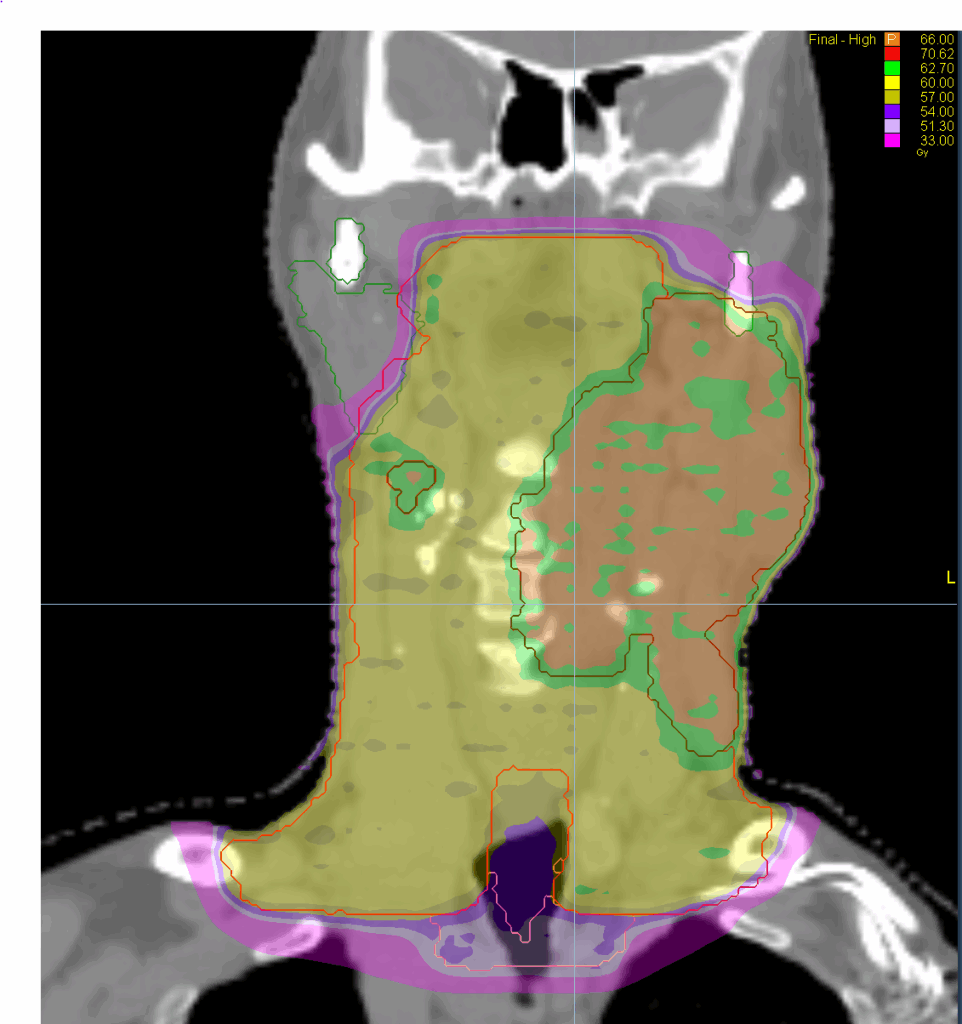

Treatment Plan Images

Fractionation / Protocol Used

66/60/54 Gy in 33 fractions

PTV(s) Volume, Length

967 cc, 21 cm

- TomoHelical™ 2.5 cm